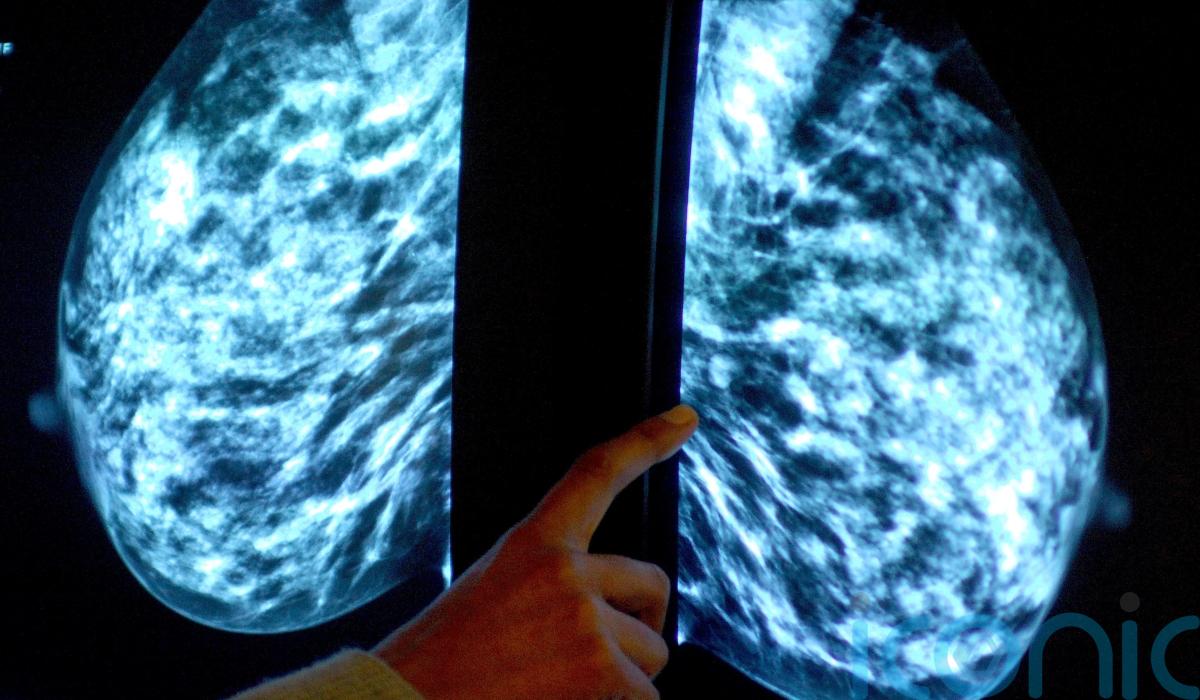

Women who use a contraceptive coil may have a slightly higher risk of developing breast cancer, new research suggests.

The study found an “unexpected” association between the use of an intrauterine system (IUS), also known as an hormonal coil, and an increased risk of the cancer in women aged 15 to 49.

According to the findings, there were 14 extra cases of breast cancer per 10,000 women using a levonorgestrel-releasing intrauterine system (LNG-IUS) for five years, compared with a similar number of women not using the contraception.

Research has found that prolonged use of the contraceptive pill slightly increases breast cancer risk, but it was thought that using the coil would not increase breast cancer risk because of the much lower levels of hormone exposure to the whole body.